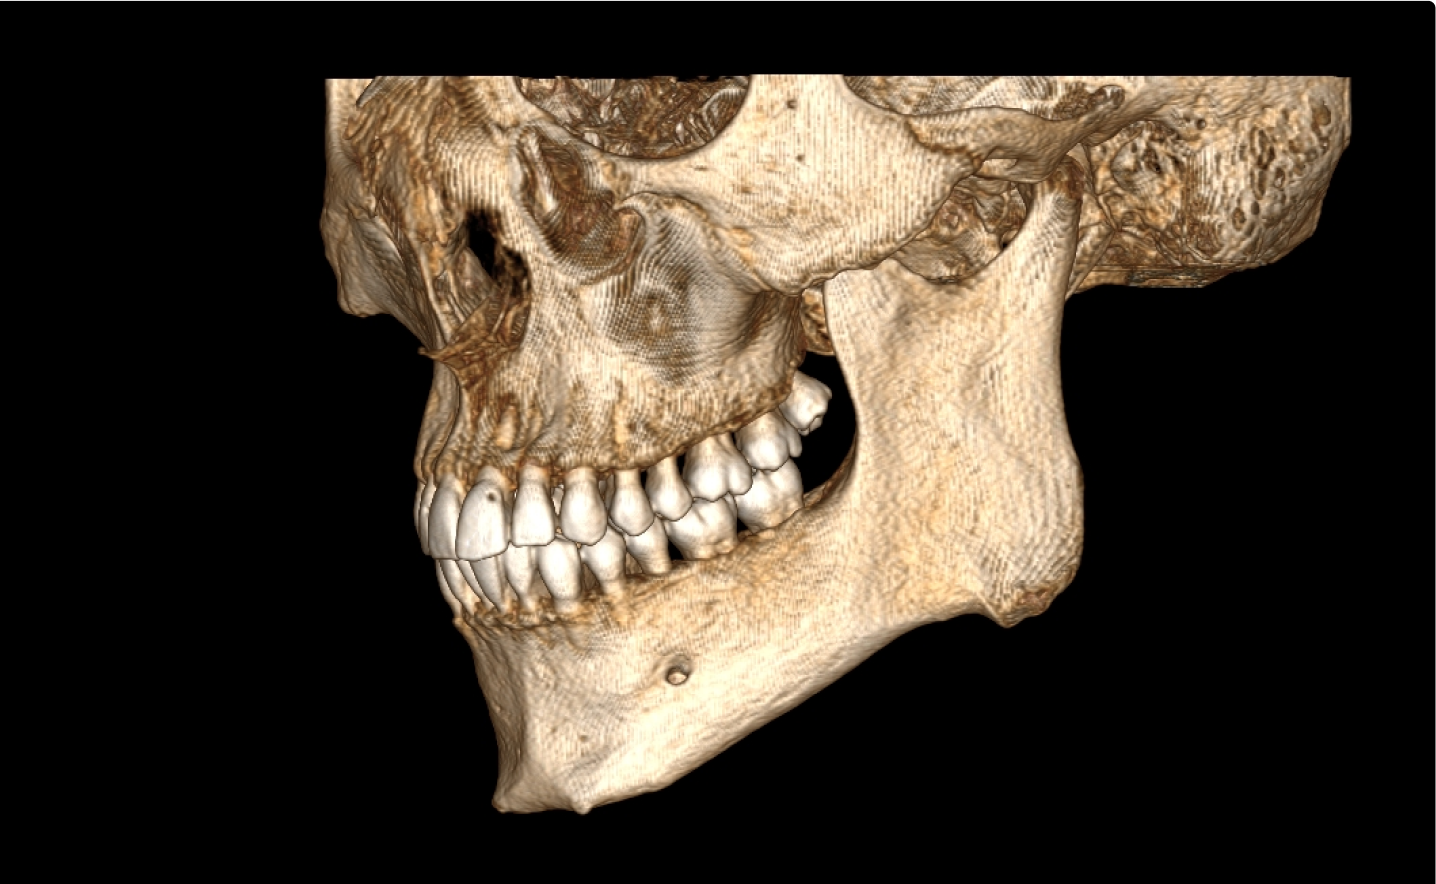

Мультиспиральная дентальная компьютерная томография (МДКТ или, как ее еще называют, КТ зубов) – это современный высокоточный метод лучевой диагностики, с помощью которого получают объемные цифровые изображения всей зубочелюстной системы. В основе метода лежит применение рентгеновского излучения и последующая цифровая обработка полученных данных специальными компьютерными программами.

Мультиспиральный томограф выполняет послойное сканирование области верхней и нижней челюстей с помощью рентгеновских лучей, а затем, используя компьютерную обработку данных, создает 3D-модели исследуемой зоны. Современные модели томографов проводят круговое сканирование по спирали, делая срезовые снимки на расстоянии 0,5 мм друг от друга. Затем на основе этих данных реконструируются детальные изображения челюстно-лицевой области в трехмерном формате.

В отличие от конусно-лучевой компьютерной томографии (КЛКТ), которая также в последнее время применяется в стоматологии, МДКТ помогает лучше визуализировать костные структуры на фоне артефактов от имплантов и протезов, выполнить сканирование быстрее, без двигательных артефактов, в любом объеме под запрос вашего ортодонта.

- Информативность. Дентальная КТ позволяет обнаружить признаки патологии, которые не видны на обычных (2D) панорамных снимках – ортопантомограммах. На двухмерных рентгенограммах различные структуры накладываются друг на друга. В отличие от этого пространственные модели дают возможность рассмотреть челюстно-лицевой аппарат в различной проекции и плоскости.

- Широкие возможности диагностики. На трехмерных изображениях можно увидеть в целом верхнюю и нижнюю челюсть, включая гайморовы пазухи, височно-нижнечелюстные суставы. Помимо костной ткани при проведении КТ можно оценить состояние окружающих мягких тканей. Это бывает особенно важно при выборе оптимального способа протезирования и имплантации, при подозрении на опухолевые процессы, при планировании оперативного вмешательства.

Высокая информативность исследования за счет детальных снимков и наглядных пространственных 3D-реконструкций позволяет увидеть то, что недоступно для визуального осмотра и обычного рентгеновского обследования.